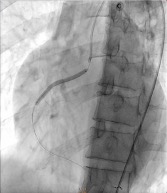

Percutaneous coronary intervention was initiated. A Xience Alpine 3.0 x 38mm drug-eluting stent (DES) was positioned at the mid to distal RCA and deployed at 16 atm and post-dilated using the same stent balloon inflated at 18 atm. Another Evermine 3.5 x 48mm drug-eluting stent (DES) was positioned at the proximal RCA and deployed at 18 atm and post-dilated using the same stent balloon inflated at 18 atm. Further dilation of the distal RCA was done using a Mini Trek 2.0 x 15mm balloon and inflated at 12 atm. However, j ust a few minutes after placing the stent. There was noted recurrence of the ST elevation on the cardiac monitor. A second look angiogram was immediately performed to check the patency of the stents. Immediately, manual distal displacement using the same stent balloon was done to displace the thrombus. Repeat angiogram showed TIMI II flow on the right coronary artery and resolution of the ST segment elevation.